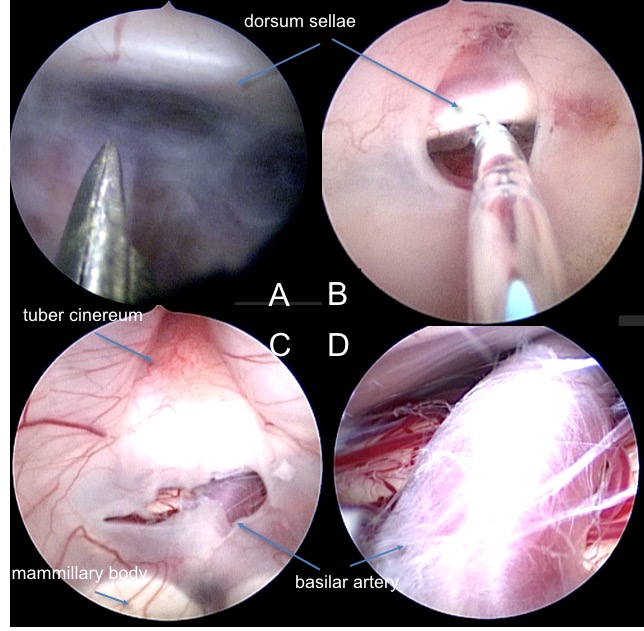

- identification des repères intraventriculaires du V3 : corps mamillaires, tuber cinereum

- identification des repères extraventriculaires : terminaison basilaire, lame quadrilatère du sphénoïde

- perforation du plancher entre lame quadrilatère du sphénoïde et tronc basilaire

A perforation du plancher aux ciseaux entre dorsum sellae et tronc basilaire ; B élargissement de l’orifice avec le neuroballoon ; C stomie ; D inspection cisternale - retrait de l’endoscope, obturation de la cheminée par surgicel tassé, suture durale si possible (au prolene)